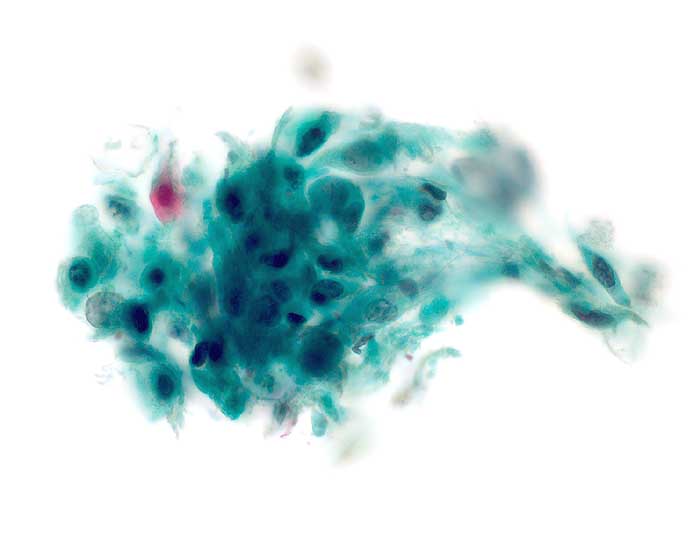

Die Tumorzellen liegen einzeln oder in kleinen Verbänden und ganzen Gewebsfragmenten. Die polymorphen Kerne sind vergrössert und enthalten verklumptes unregelmässig verteiltes Chromatin und grosse Nukleolen. Gut differenzierte Karzinome erkennt man am breiten und oft verhornten Zytoplasma. Längliche bis fadenförmige Tumorzellen mit pyknotischen Kernen können als einziger Hinweis auf das Vorliegen eines Karzinoms vorhanden sein. Wenig differenzierte Karzinome haben polymorphe und schlechter erhaltene Kerne. Der Hintergrund ist meist detritisch und oft hämorrhagisch. Ulzeration, Einblutungen und bakterielle Infektionen beeinflussen den Erhaltungszustand und die Art der abgestrichenen Zellen. Ist die Oberfläche eines ulzerierten Karzinoms von einem Fibrinschorf bedeckt, enthalten die Ausstriche lediglich Detritus, Granulozyten und Erythrozyten, aber keine Tumorzellen. Die Sensitivität für die Karzinomdiagnose ist aus diesem Grund geringer als für die Diagnose eines Carcinoma in situ.